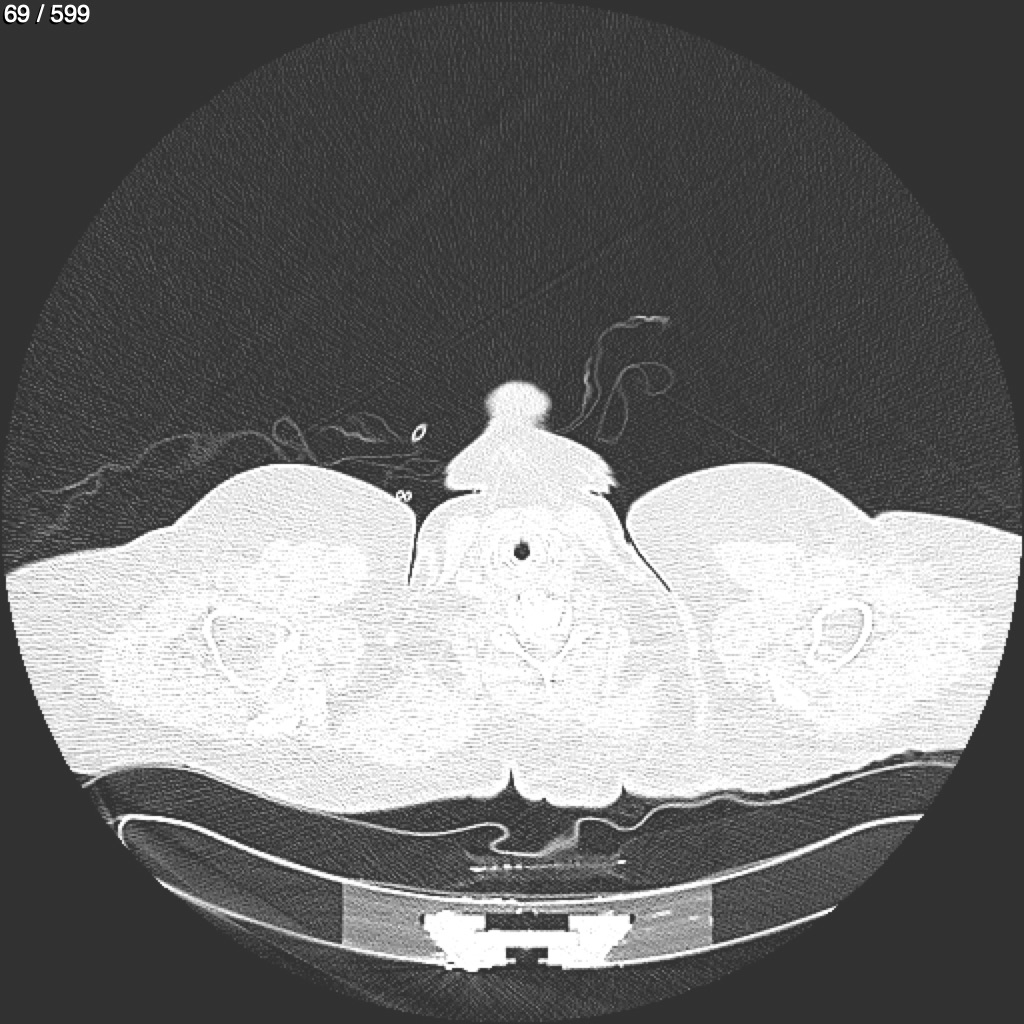

Home G​l​o​r​i​a​ ​G​l​a​d​y​s​ ​B​e​a​s​l​e​y​ ​-​ ​T​ó​r​a​x​ ​T​o​r​a​x​_​S​i​m​p​l​e​ ​(​A​d​u​l​t​o​)